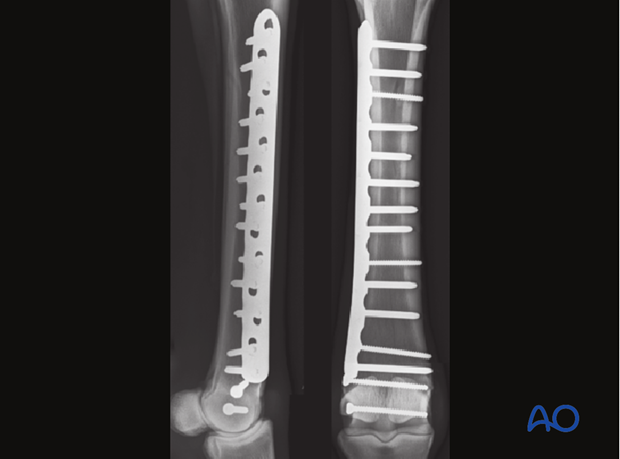

A plate of appropriate dimensions is selected. In metacarpal fractures, a 10-11 hole broad 4.5 mm plate is usually used and in metatarsal fractures, a 12-13 hole plate is used in an average sized race horse. Although, traditional plates can be used successfully, locking compression plates (LCPs) are probably superior.

The remaining screw holes are filled with appropriate length 5.0 mm locking head screws.

As with an open exposure, approximately three cortex screws (one at the proximal and distal end of the plate and one in its center) are placed to pull the plate against the bone. The distal cortex screws in the plate can be placed in lag fashion if the fracture configuration allows it. The remainder of the technique is identical to that described above using locking head screws, except that one is working through small incisions over each hole in the plate. The stab incisions must be large enough to allow secure insertion of locking guides into the plate.